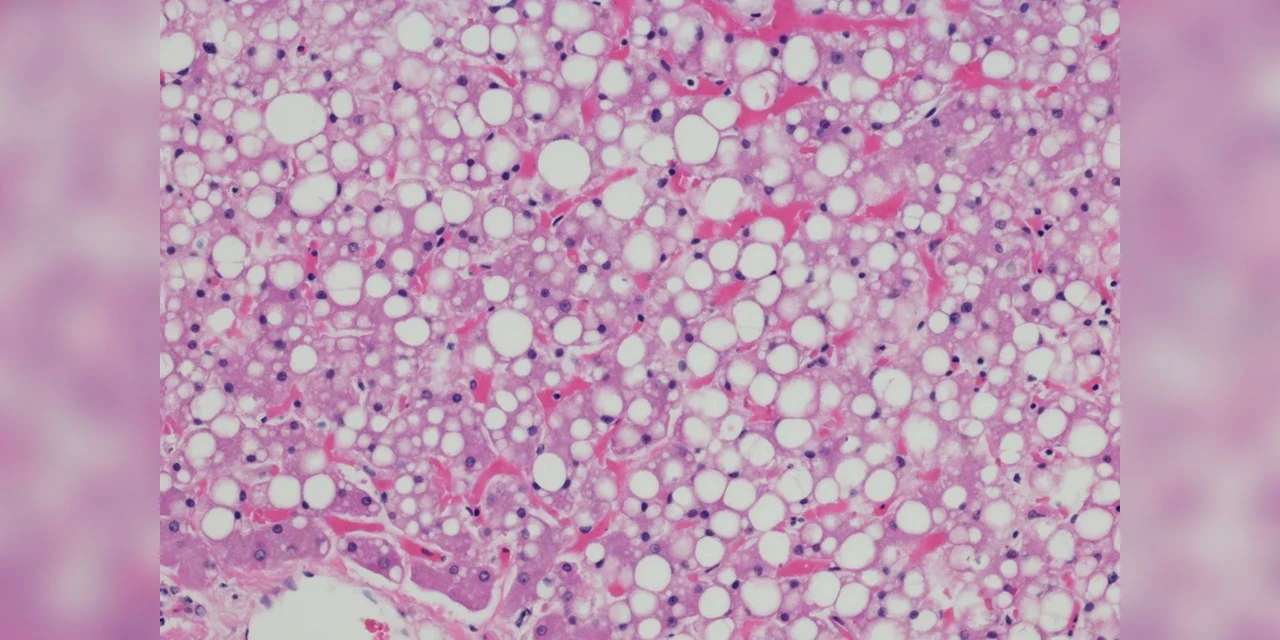

Cada vez mais comum entre os brasileiros, a esteatose hepática, conhecida popularmente como gordura no fígado, tem se tornado motivo de alerta para os profissionais de saúde. A condição é muitas vezes silenciosa, mas pode evoluir para doenças graves se não for diagnosticada e tratada a tempo.

“O problema começa de forma discreta, mas pode evoluir para inflamações crônicas e fibrose, aumentando o risco de cirrose e câncer de fígado”, explica o endocrinologista Paulo Bittencourt, presidente do Instituto Brasileiro do Fígado (Ibrafig).